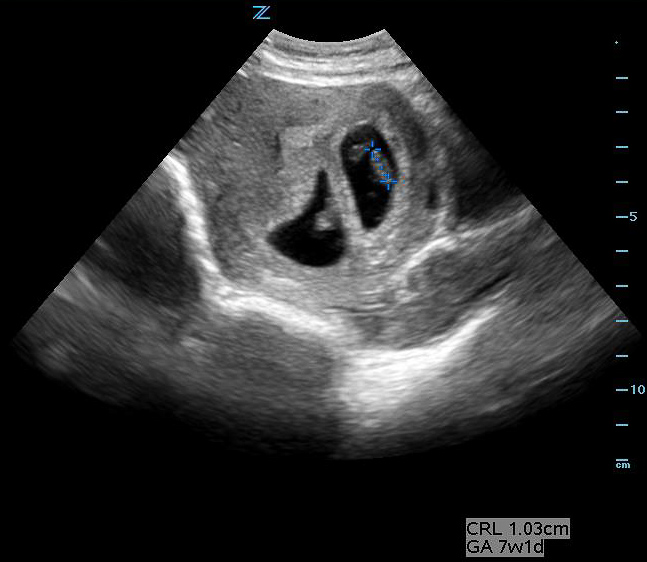

Figure 32A. Two completely separate chorionic and amniotic sacs are visible. Two different eggs were fertilized and the children will be fraternal not identical twins. Note, it can be difficult to distinguish dichorionic diamniotic from other types of twins such as diamniotic monochorionic, especially early in pregnancy.

Figure 32B. Two completely separate chorionic and amniotic sacs are visible. Two different eggs were fertilized and the children will be fraternal not identical twins. Note, it can be difficult to distinguish dichorionic diamniotic from other types of twins such as diamniotic monochorionic, especially early in pregnancy.